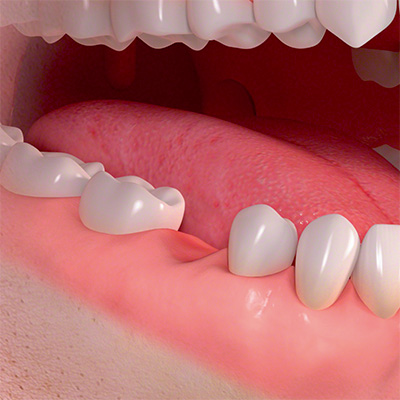

Die Gründe für Zahnverlust sind vielfältig. Die Implantologie ist die fortschrittlichste Methode, verlorene Zähne zu ersetzen und Lücken zu schließen. Sie bietet in nahezu jeder Situation eine flexible und zahnsubstanzschonende Lösung. Implantatgetragene Zähne vermitteln das Gefühl eigener Zähne. Sie fühlen sich an wie Natürliche, sitzen fest und fügen sich harmonisch in die individuelle Zahnumgebung ein. Auch bei totalem Zahnverlust ermöglichen Implantate eine ästhetische und festsitzende Versorgung. Die dentale Implantologie eröffnet uns die Möglichkeit, Patienten in nahezu jeder Situation einen festsitzenden Zahnersatz anzubieten. Implantatgetragene Prothesen sitzen fest und rutschen nicht. Schmerzfreies Kauen wird zur Realität.

In unserer Praxis werden die Implantate gesetzt (Implantatchirurgie) und auch prothetisch versorgt. Die exakten Implantatpositionen werden durch die prothetische Fallanalyse erarbeitet. Wir arbeiten seit über 18 Jahren in der Implantologie und stehen für Behandlungskonzepte, die Funktionalität mit hoher Ästhetik verbinden. Wir setzten und versorgen jährlich Implantate in dreistelliger Zahl.

Die Erfahrung mit unseren Patienten zeigt: Implantate können das Leben verändern. Sie sorgen für eine bessere Lebensqualität.